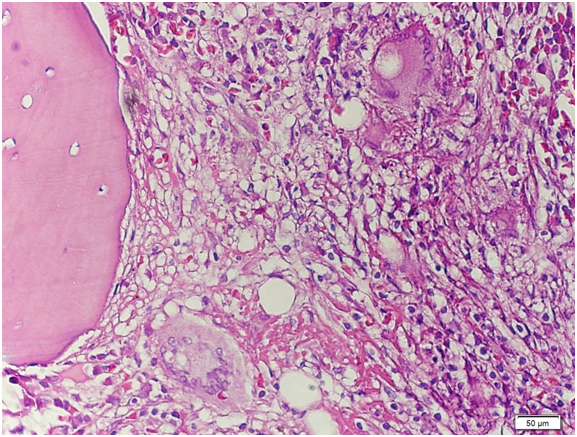

Figure 14 High‒power view. There is significant granuloma formation with Langhans type giant cell (arrows) focally scattered in the marrow matrix. The residual marrow shows erythrogranulopoiesis with maturation. Megakaryocytes are adequate.